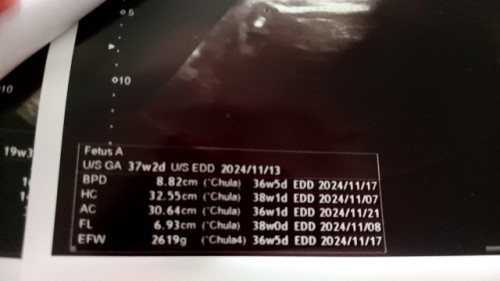

แม่บ้านนี้ เดินขายของฉ่ำ นน. ตัวน้อง ถือว่าเกินเกณฑ์ มั้ยคะ ท้องแรก คลอดง่ายมาก แต่ นน.แรกคลอด แค่ 2720 เอง ท้องที่ 2 อายุครรภ์ 34+4 มาตั้ง 2619 แล้วว คุณหมอบอก คลอดง่ายกว่าท้องแรกแน่ๆ แม่หวั่นๆ กลัวจะแตก ก่อน 37 วีคค่ะ .... แม่คลอดธรรมชาติค่ะ กลัวว่า ถ้าน้อง นน. ตัวมากเกิน จะคลอดยากค่ะ #ขอคำแนะนำกับแม่ๆด้วยนะคะ